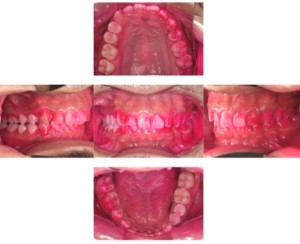

歯周病検査(治療前)

症例

歯周病検査(治療後)

基本情報

年齢・性別 41歳・男性

主訴 主訴:歯ぐきから出血する

治療部位:全顎

治療内容 1.歯周ポケット検査、資料取り(レントゲン写真14枚・口腔内写真)、歯磨き指導

2.歯磨き指導チェック、縁上の歯石除去

3.縁下の歯石除去4回

4.再評価(歯周ポケット検査・レントゲン写真14枚・口腔内写真)

5.メインテナンス

治療費 合計:14,160円

内訳(全て保険診療3割負担)

・初診検査、歯磨き指導、縁上の歯石除去:3,630円

・レントゲン写真、縁下の歯石除去①:3,040円

・縁下の歯石除去②:1,530円

・歯磨き指導チェック、縁下の歯石除去③:2,070円

・縁下の歯石除去④:1,530円

・再評価:2,360円

(2022年5月現在現在)

担当者所見 全体的に出血が見られたのと、奥の歯ぐきは炎症があり歯周ポケットが深かった為、まずは歯ブラシの当て方+歯間ブラシ3Sサイズを使用して頂き炎症を落ち着かせました。

両方毎日使用して頂いた為、スムーズに歯周病治療を行うことができました。毎日のホームケアが不十分だと、なかなか結果に繋がらず、治療期間も長くかかってしまう為、患者様の協力が歯周病治療を成功させるためにはかなり重要になっていきます。

そして一度病気になった歯ぐきは再発しやすい為、今後は3ヶ月に1度の定期的なメインテナンスで、この状態を維持できるよう一緒に管理していきます。